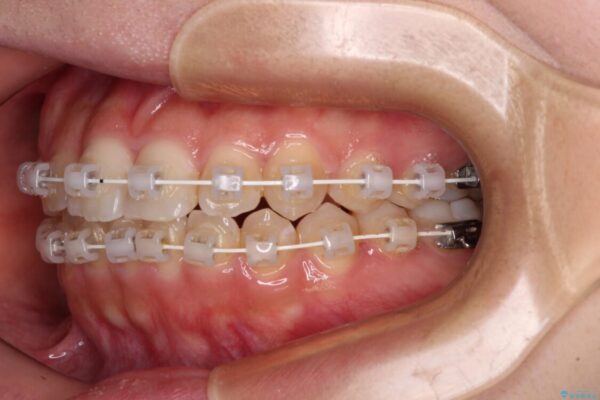

マウスピース矯正のような自己管理の煩わしさは避け、早く治療を終えたいとのことで、ワイヤー装置による矯正治療を行うこととしました。

治療途中

• 【モニター】短期間で終わりたい ワイヤー装置での非抜歯矯正 治療途中画像